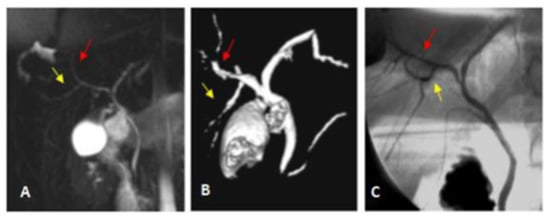

| Type III | Anomalous RPSD insertion | 4 (11.4) | 4 (11.4) | |

| A | Insertion of RP into the LT hepatic duct | 2 | 2 | |

| B | Insertion of RP into the CHD | 2 | 2 | |